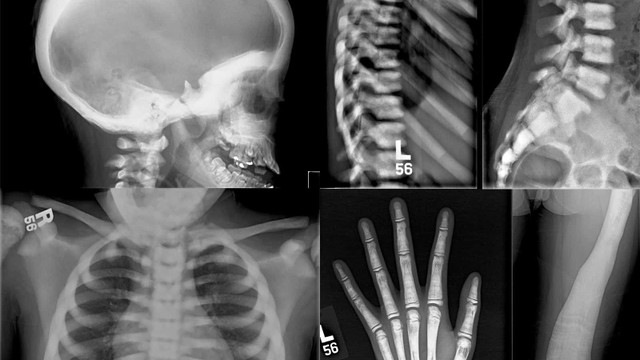

Cứng khớp là triệu chứng mà nhiều người gặp phải, đặc biệt là ở người cao tuổi. Đây là triệu chứng không nguy hiểm đến tính mạng nhưng sẽ gây hạn chế hoạt động hằng ngày của bạn. Hãy đến gặp bác sĩ để được chẩn đoán và tư vấn phương pháp khắc phục triệu chứng này và nâng cao chất lượng cuộc sống.